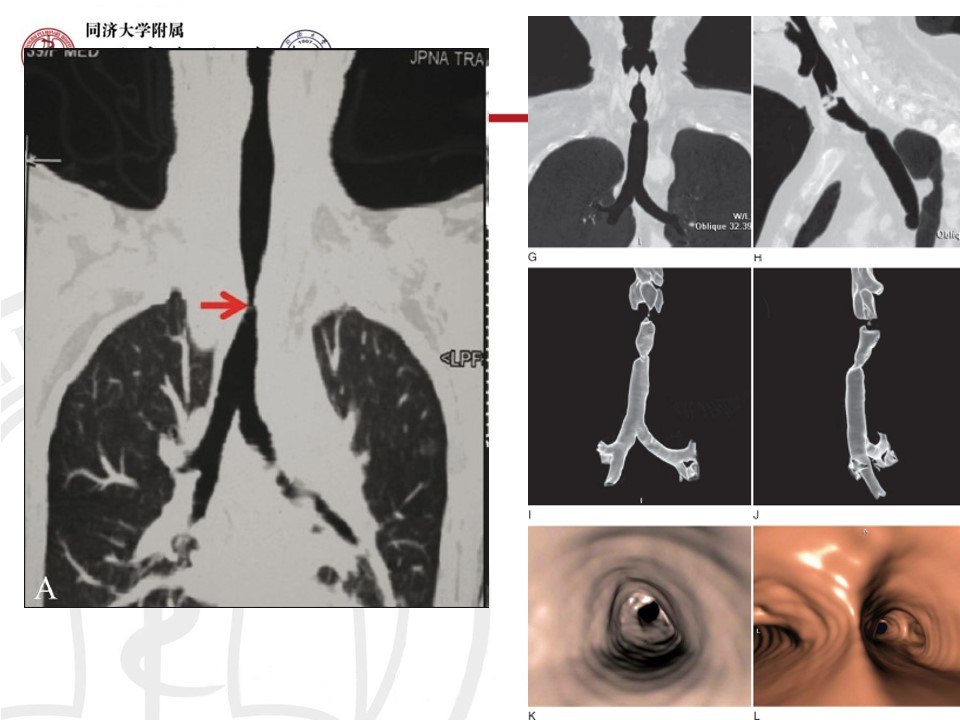

先心致气管狭窄

图片尺寸2500x1787